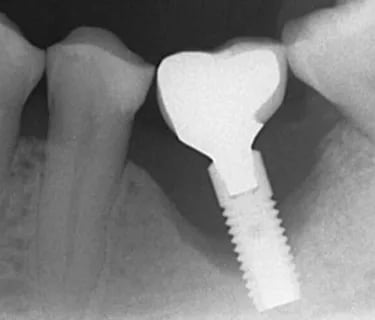

O implante é integrado ao osso através de um processo chamado osseointegração.

Quando essa união está estável, ele funciona como uma raiz artificial fixa.

Se existe movimento, alguma estrutura está falhando — e nem sempre é o implante.

A avaliação clínica e radiográfica define o diagnóstico.